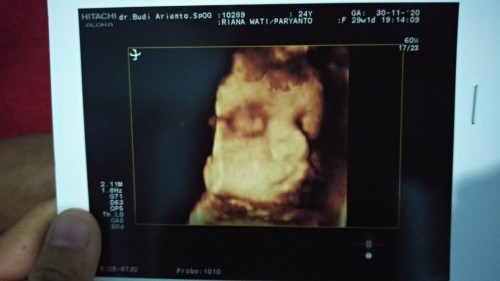

Alhamdulillah 26w2d meskipun banyak yang bilang kecil perutnya aku gak ambil pusing karna tiap bulan priksa dan bidan nya pun bilang semuanya normal 😊 Sehat terus dek 😘 Hpl februari apa yang udah dirasain mak ? Kalo saya alhamdulillah geraknya sudah aktif apa lagi kalo abis makan sama malam hari. #firstbaby #firstbaby #firstbaby